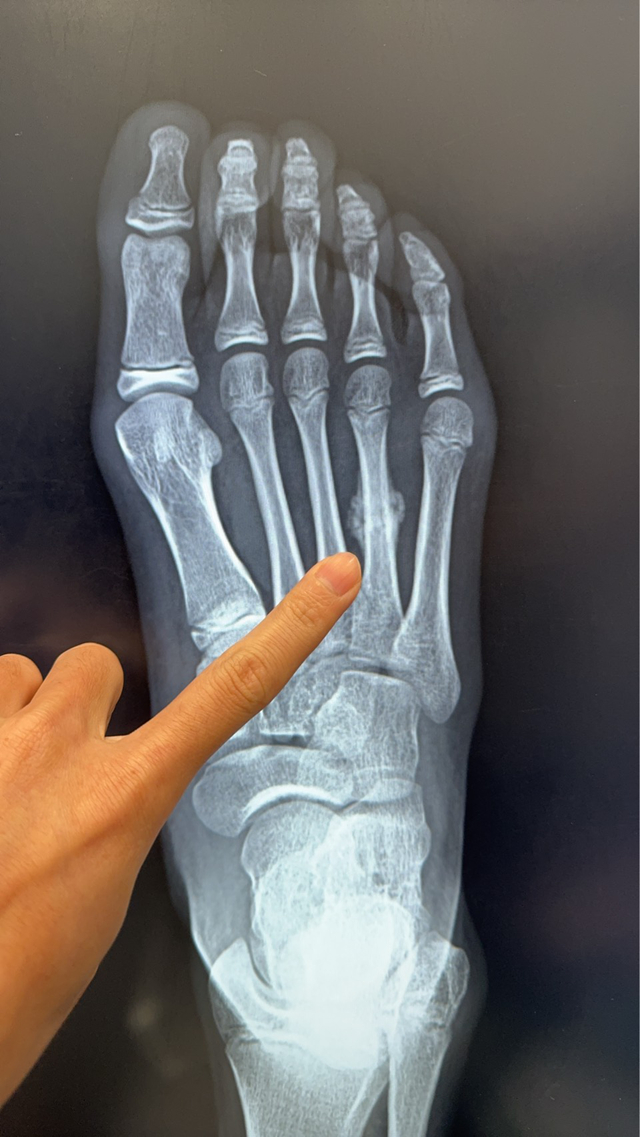

陳建宏骨科診所近日接獲一名11歲女學童就醫個案,該學童因暑期密集參加田徑與球類訓練,右側腳掌疼痛兩周未緩,檢查後確診為「蹠骨應力性骨折」,且已出現癒合跡象。

陳建宏醫師說明,蹠骨位於腳掌前端,承受人體走路、跑跳時的主要壓力。當骨頭長期反覆承受過大的應力,而缺乏足夠休息與修復時間時,便可能出現顯微的骨折,這就是所謂的「應力性骨折」。

與一般一次性外力造成的骨折不同,「應力性骨折」大都是長時間累積而成,初期症狀並不明顯,容易被誤為只是一般的拉傷或扭傷。就像此位11歲的小妹妹,問診詢時已經不舒服兩周,當初本以為只是單純扭到,沒想到卻已經骨折了。